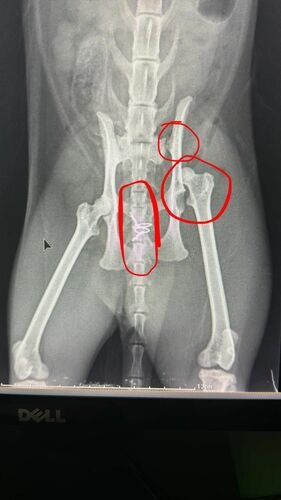

Meu gato Romeu foi atropelado dia 09/04/24 perto das 20h. No mesmo dia passou por uma cirurgia de emergência chamada “Hernioplastia” (A hérnia dele se rompeu deixando o intestino dele solto pelo corpo). Além disso o Romeu fraturou 3 ossos, sendo 2 na perna e 1 na parte de cima dele. Acontece que todos os nossos fundos foram na cirurgia de Hernioplastia, e precisamos de dinheiro para fazer a segunda cirurgia dele para corrigir os ossos quebrados…

Estamos desesperados pois ja pagamos um valor altíssimo na primeira cirurgia e agora não temos como pagar a segunda. O Romeu pode ficar sem o movimento da perninha sem a cirurgia.